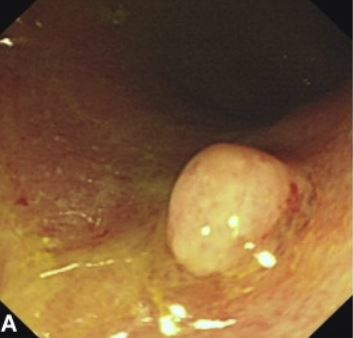

潰瘍性大腸炎と誤診され急激に悪化した大腸のDLBCLリンパ腫

最初の内視鏡と生検で「潰瘍性大腸炎」と診断されたが治療が全く効果が無く、2度目の内視鏡の生検でリンパ腫と診断。初発であり「長期経過の潰瘍性大腸炎に悪性リンパ腫が発生した」ものではなく「腸炎様のリンパ腫」であると結論している。過去に20件ほどの“colitis-like”

diffuse-type colorectal lymphomaの報告があるとのこと。